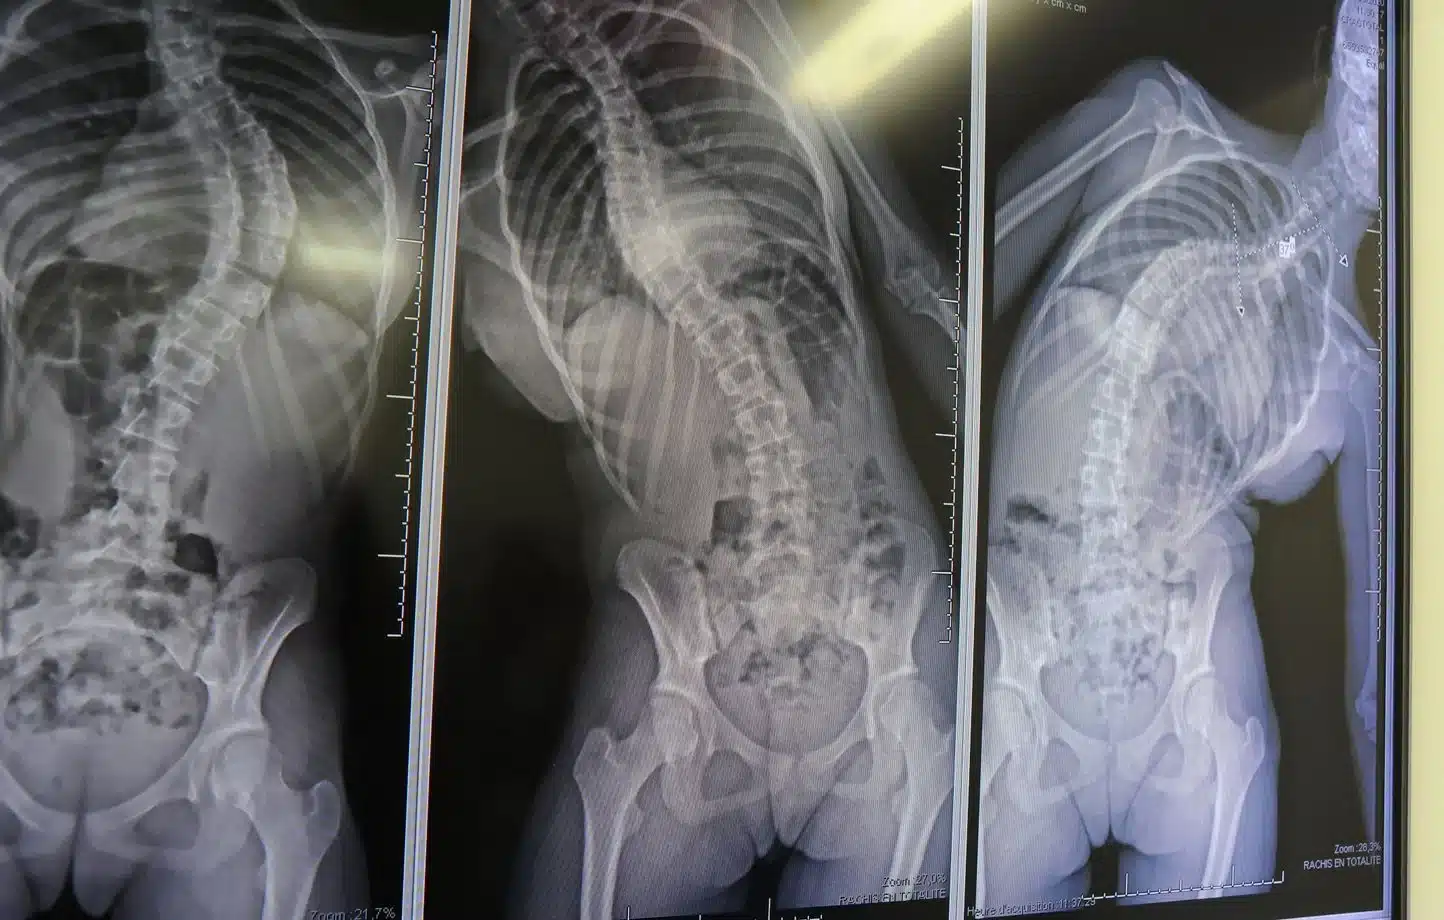

La scoliose n’est pas rare, mais certains cas sont si complexes qu’ils nécessitent des interventions hors du commun. Pour cette jeune patiente britannique, les choses ont empiré très rapidement. En quelques mois, la courbure de sa colonne vertébrale s’est aggravée au point de comprimer ses poumons, mettant sa santé en grave danger.

L’opération menée à Shanghai était loin d’être ordinaire. Le professeur Junlin Yang et son équipe ont dû mobiliser des techniques chirurgicales avancées pour redresser la colonne vertébrale de la jeune fille.

- Dérotation : Une procédure minutieuse pour réaligner la colonne vertébrale et corriger la torsion sévère.

- Ostéotomie : Une technique exigeant une coupe chirurgicale sur des segments osseux pour restaurer leur position correcte.

- Fixation par vis : L’utilisation de matériel médical spécialisé pour stabiliser durablement la colonne après les corrections apportées.

L’opération, qui a duré quatre heures, a permis de rectifier une courbure impressionnante de 100 degrés, tout en restaurant la bonne capacité respiratoire, gravement compromise auparavant.

Les résultats de cette opération sont tout bonnement spectaculaires. La jeune patiente, auparavant penchée sous le poids de sa double scoliose, a retrouvé une posture droite, signe visible de l’efficacité de cette intervention sans précédent.

Mais ce n’est pas tout. L’opération a permis à l’adolescente de bénéficier directement d’une amélioration nette de ses capacités pulmonaires, insuffisantes à cause de la compression exercée sur ses poumons. Et détail impressionnant, elle a même gagné plusieurs centimètres en taille, une transformation qui témoigne de l’ampleur du redressement effectué sur sa colonne vertébrale.